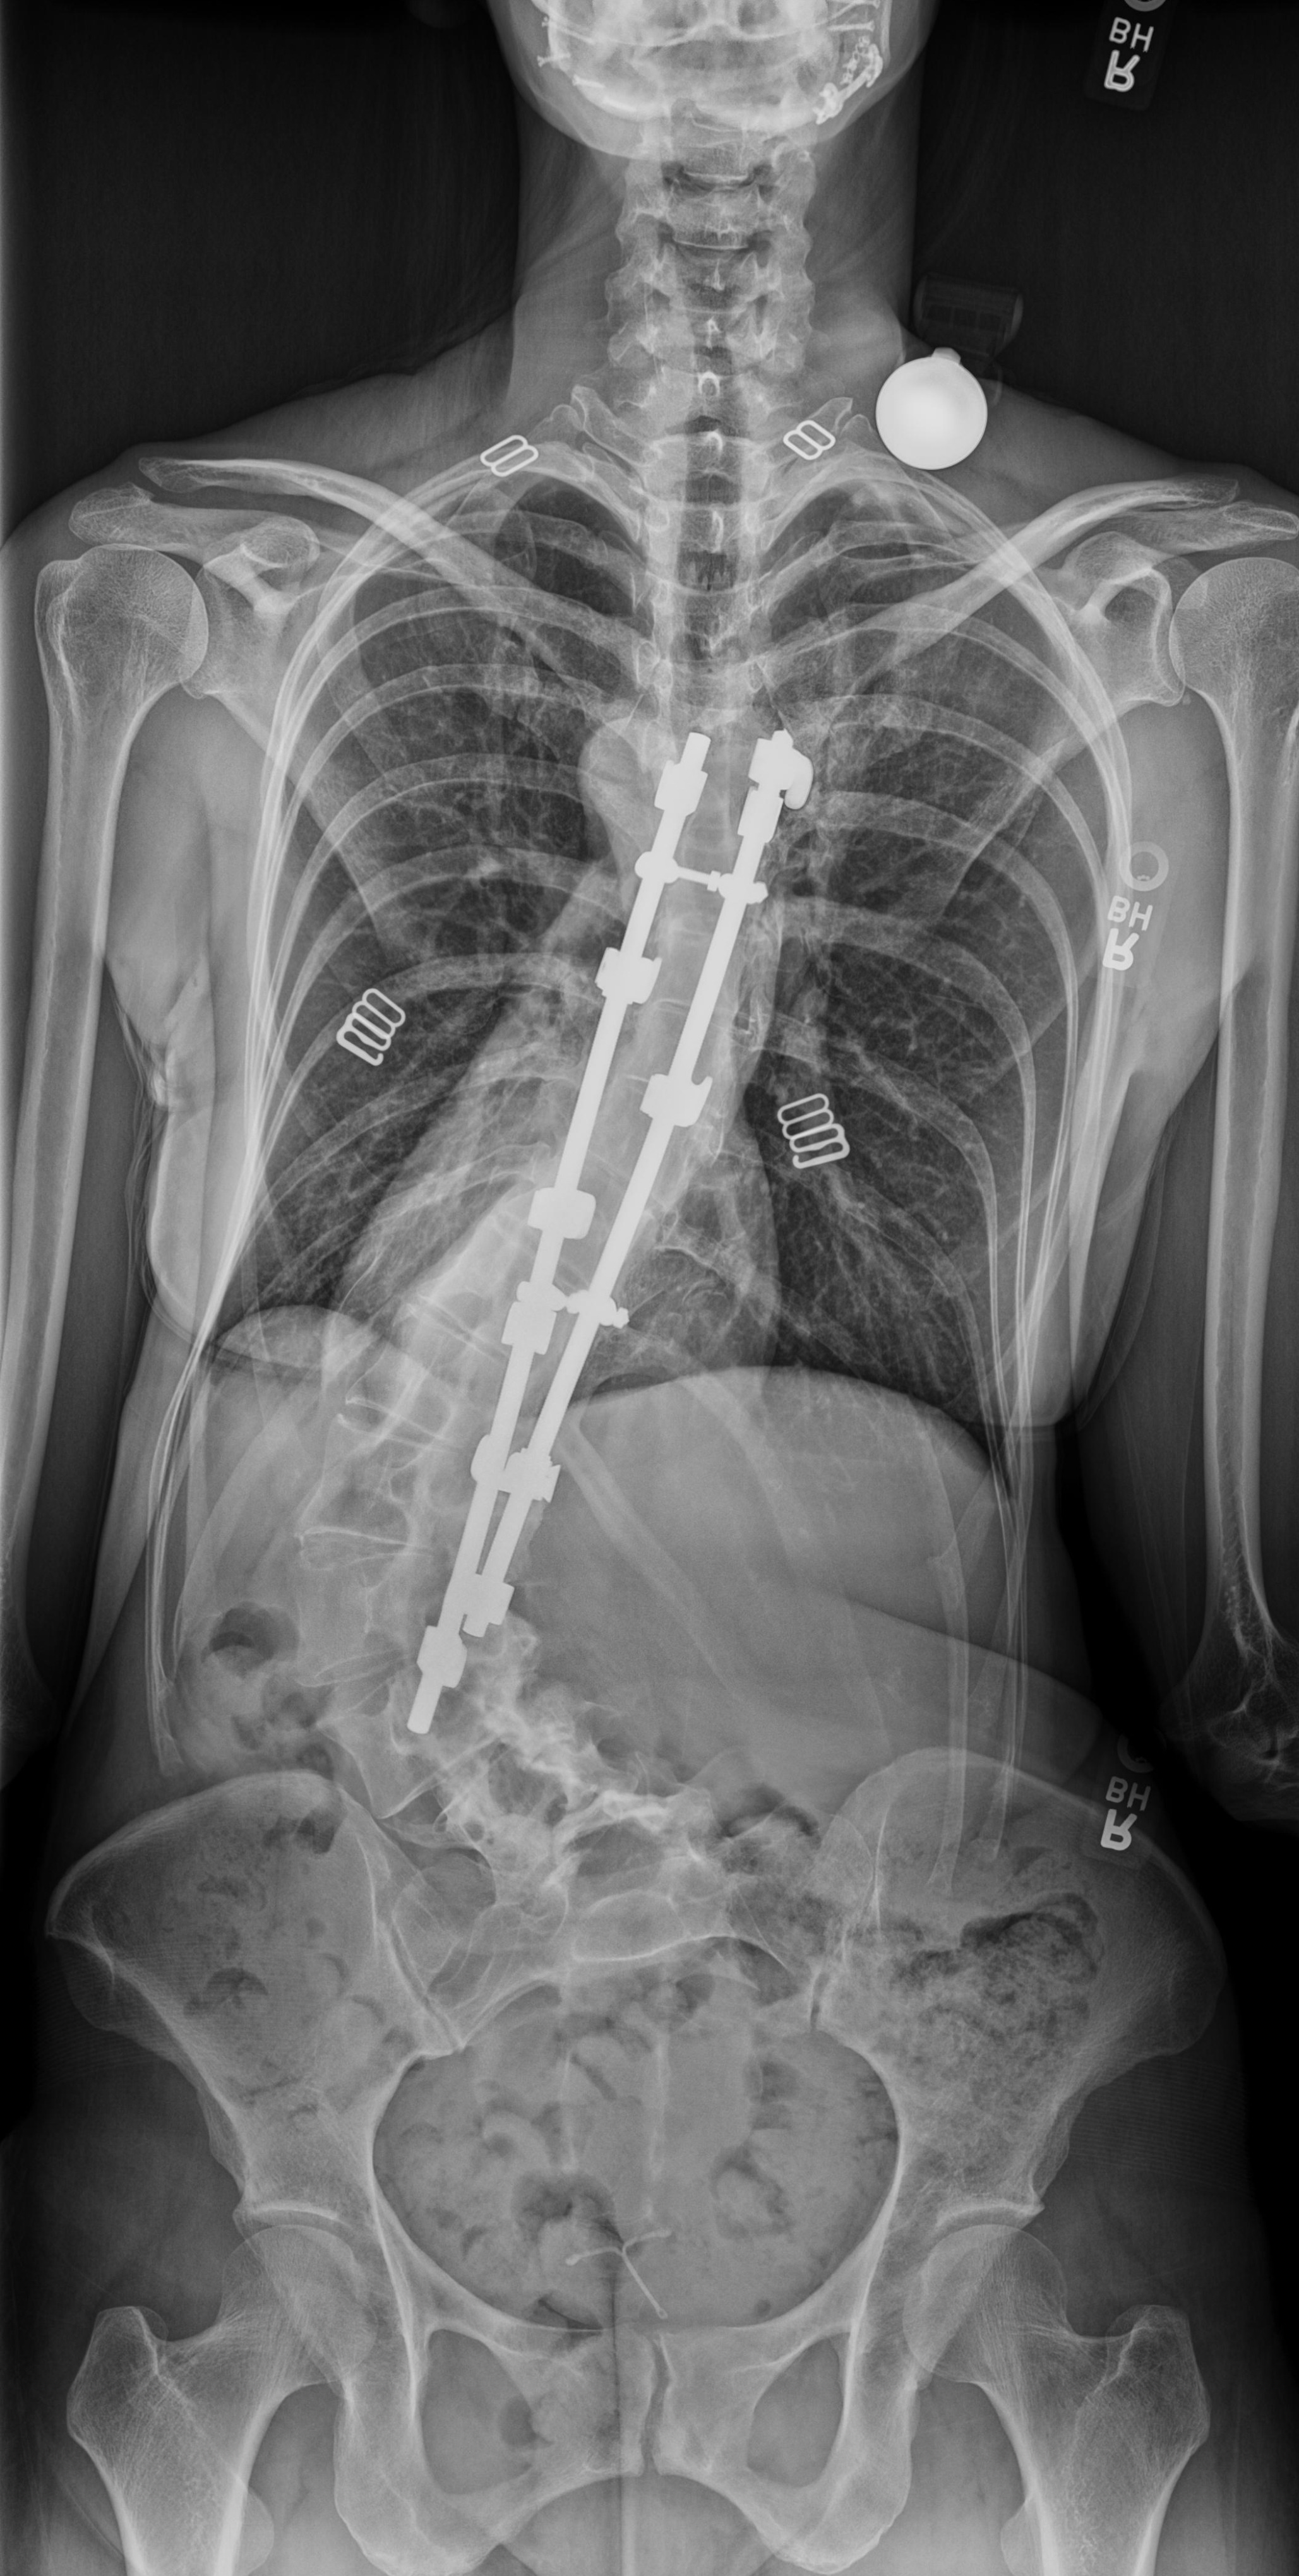

At age 11, Julie was diagnosed with severe idiopathic juvenile scoliosis, which is an abnormal curvature of the spine. Two years later, she was referred to specialists in Utah for corrective surgery. In a tragic twist of fate, the surgeons accidentally damaged her spinal cord during the spinal fusion. What resulted was permanent loss of sensation in her right leg. Though still able to walk and hike, which she adores, now, 36 years later, we are seeing the full impact of the damage done. Because her spine is continuing to collapse, Julie is experiencing symptoms of progressive nerve damage to her left leg and is running out of time.

- Surgery: The surgery is grueling and will entail removing old hardware, fusing her spine from T5-SI (into the pelvis), and fixing the broken vertebra and slipped discs. This type of procedure can run upward of $250,000, and her initial out-of-pocket costs may exceed $60,000, not including loss of income.